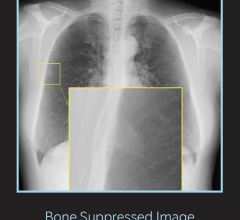

Genomics has guided personalized cancer treatments for the past two decades. Now, AI biomarkers are expanding the field, helping radiologists and radiation oncologists stratify risk and potentially plan more precise treatments. Unlike traditional biomarkers, “AI analyzes images of a patient’s biopsy

Genomics has guided personalized cancer treatments for the past two decades. Now, AI biomarkers are expanding the field ...